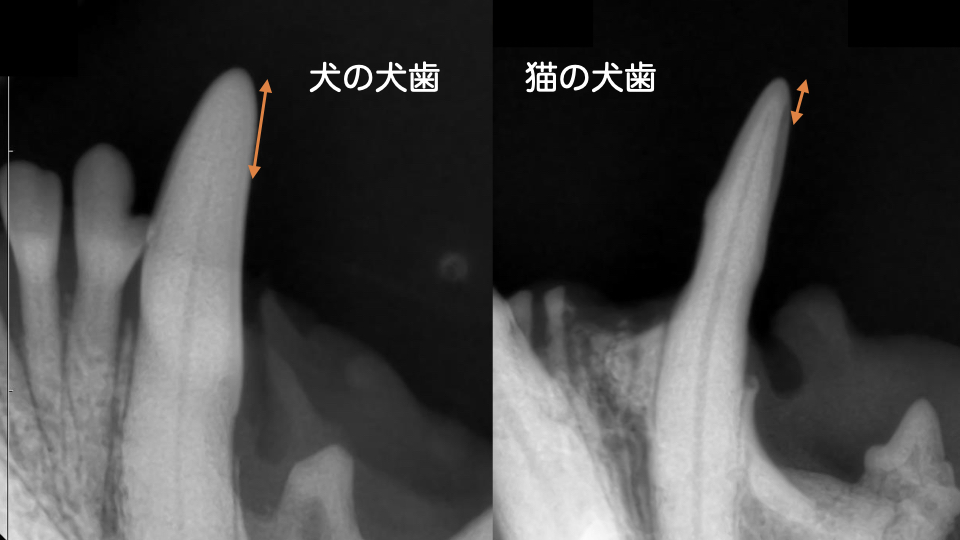

下のレントゲン写真を見てみましょう。

左が犬の犬歯、右が猫の犬歯です。

オレンジの矢印は歯の先端から歯髄腔までの距離です。

猫は歯の先端ギリギリまで歯髄腔が伸びており、神経が通っています。